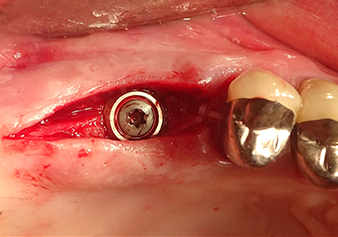

Dopo un controllo intermedio (Fig. 4) è stata eseguita un'ulteriore fase di preparazione (Fig. 5). Lo strumento idraulico Z35P è stato utilizzato in un secondo momento per sollevare la membrana sino alla posizione desiderata (Fig. 6 e 7). In seguito alla suddetta operazione, si è proceduto ad una ulteriore preparazione piezochirurgica della sede dell'impianto conclusasi con l'applicazione della fresa e della fresa a spallamento sul diametro dell'impianto di 4,8 mm. Il materiale di rinforzo (dimensione delle particelle di ca. 0,8 - 1,6 mm) è stato introdotto sotto la membrana di Schneider prima che venisse inserito l'impianto (Fig. 8).

Impianto e ricostruzione protesica

L'impianto è stato inserito manualmente e molto lentamente affinché il materiale di rinforzo potesse essere spostato atraumaticamente nella direzione del seno mascellare (Fig. 9). Nel corso del processo, la membrana è stata nuovamente spinta in direzione craniale. Due mesi dopo, il sito chirurgico si era cicatrizzato senza irritazioni. A distanza di sei mesi, la radiografia mostra un sensibile aumento dell'opacità intesa come prima comparsa di un centro di ossificazione (Fig. 10). La ricostruzione protesica è stata realizzata con una corona in metallo-ceramica.